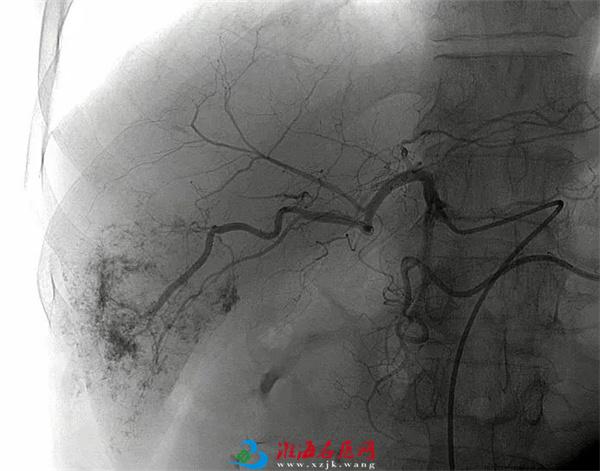

左图:术中造影示肝脏右后叶血管瘤染色明显

右图:栓塞后造影示血管瘤染色基本消失

手术日,孙晓忠和马云松医师为其行“经导管肝血管瘤造影+栓塞术”,造影显示,血管瘤已远超5公分,已刺激到肝包膜,这也正是徐先生腹痛的原因。经微导管缓慢注入“平阳霉素”和“碘化油乳剂”, 起到破坏血管内皮细胞,抑制内皮细胞再生的作用,从而在给肝血管瘤供血动脉中形成栓塞,将给肝血管瘤生长供给养分的途径切断,使其停止生长,缩小或消失,达到治疗作用。栓塞后造影显示血管瘤染色基本消失,术后病人安返病房,且CT显示病灶内碘油沉积良好,会随着时间的推移慢慢代谢掉。